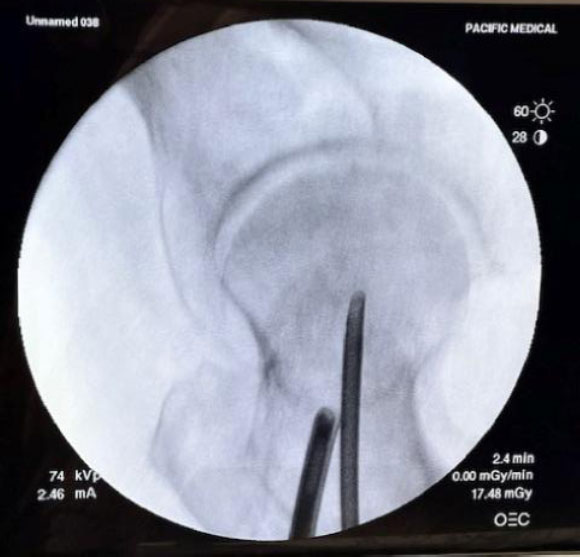

The femoral neck intramedullary cavity was large and easily visualized using standard arthroscopic tools (Fig. 3a, b – cavity and 3.5 mm shaver for scale). The cavity measured approximately 3 cm medial-lateral and 2.5 cm superior-inferior.

Arthroscope and shaver in place under fluoroscopy.

Cavity and 3.5 mm shaver for scale.

On entry, fibrofatty tissue and cancellous bone were visible (Supplementary Video 1) and easily removed with irrigation and gentle debridement (Supplementary Video 2). The inferior portion of the femoral neck appeared softer than the superior portion when probed. A clear transition was seen between the hollow femoral neck and the denser femoral head.

A biportal technique facilitated fluid inflow/outflow, visualization, and working space. Visualization remained unobstructed, and no fluid outflow compromise was noted once triangulation was achieved. Cortical bone thickness appeared unchanged on fluoroscopy post-debridement.